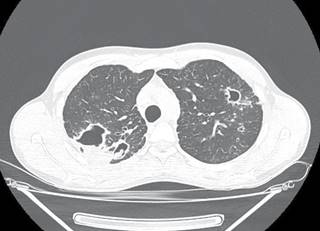

A 24-year-old male, originally from Sonora and residing in the city of Tijuana sought medical attention for his chronic respiratory symptoms. His clinical history was negative for substance abuse, and he did not report any significant illnesses in the past. Symptoms began a year earlier with cough and hemoptysis. He received private medical care, without a definitive diagnosis, and no information is available on the prescribed treatment. A chest CT showed fibrocavitary lesions in both upper pulmonary lobes, with an intracavitary mass suggestive of mycetoma (Figure 1). Given the suspicion of tuberculosis, a series of sputum smears were requested and later reported as negative, as well as an Xpert MTB/RIF (Mycobacterium tuberculosis complex not detected); as routinely done, a culture for mycobacteria was also processed. Sputum smears reported abundant spherules of Coccidioides spp.; later, a positive culture for Coccidioides spp. was reported, in addition to a positive coccidioidomycosis serology with an IgG titer of 1:64. No evidence of extrapulmonary involvement was detected during the clinical evaluation. Treatment with itraconazole 400 mg daily was started; after two months of treatment, the patient was asymptomatic and had gained 2.7 kg.